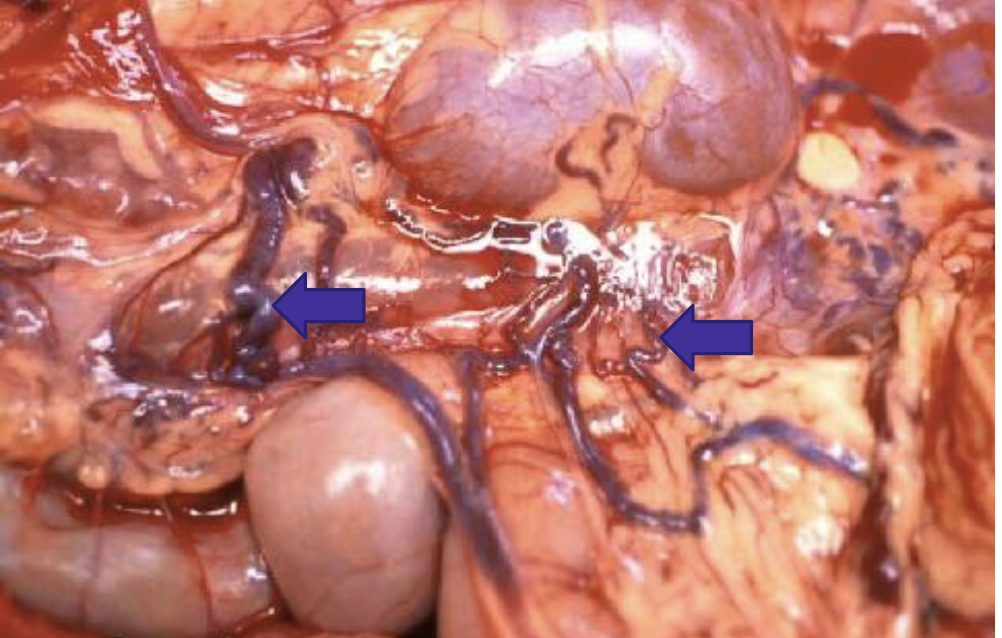

what does the image show?

acquired portosystemic shunts from portal hypertension